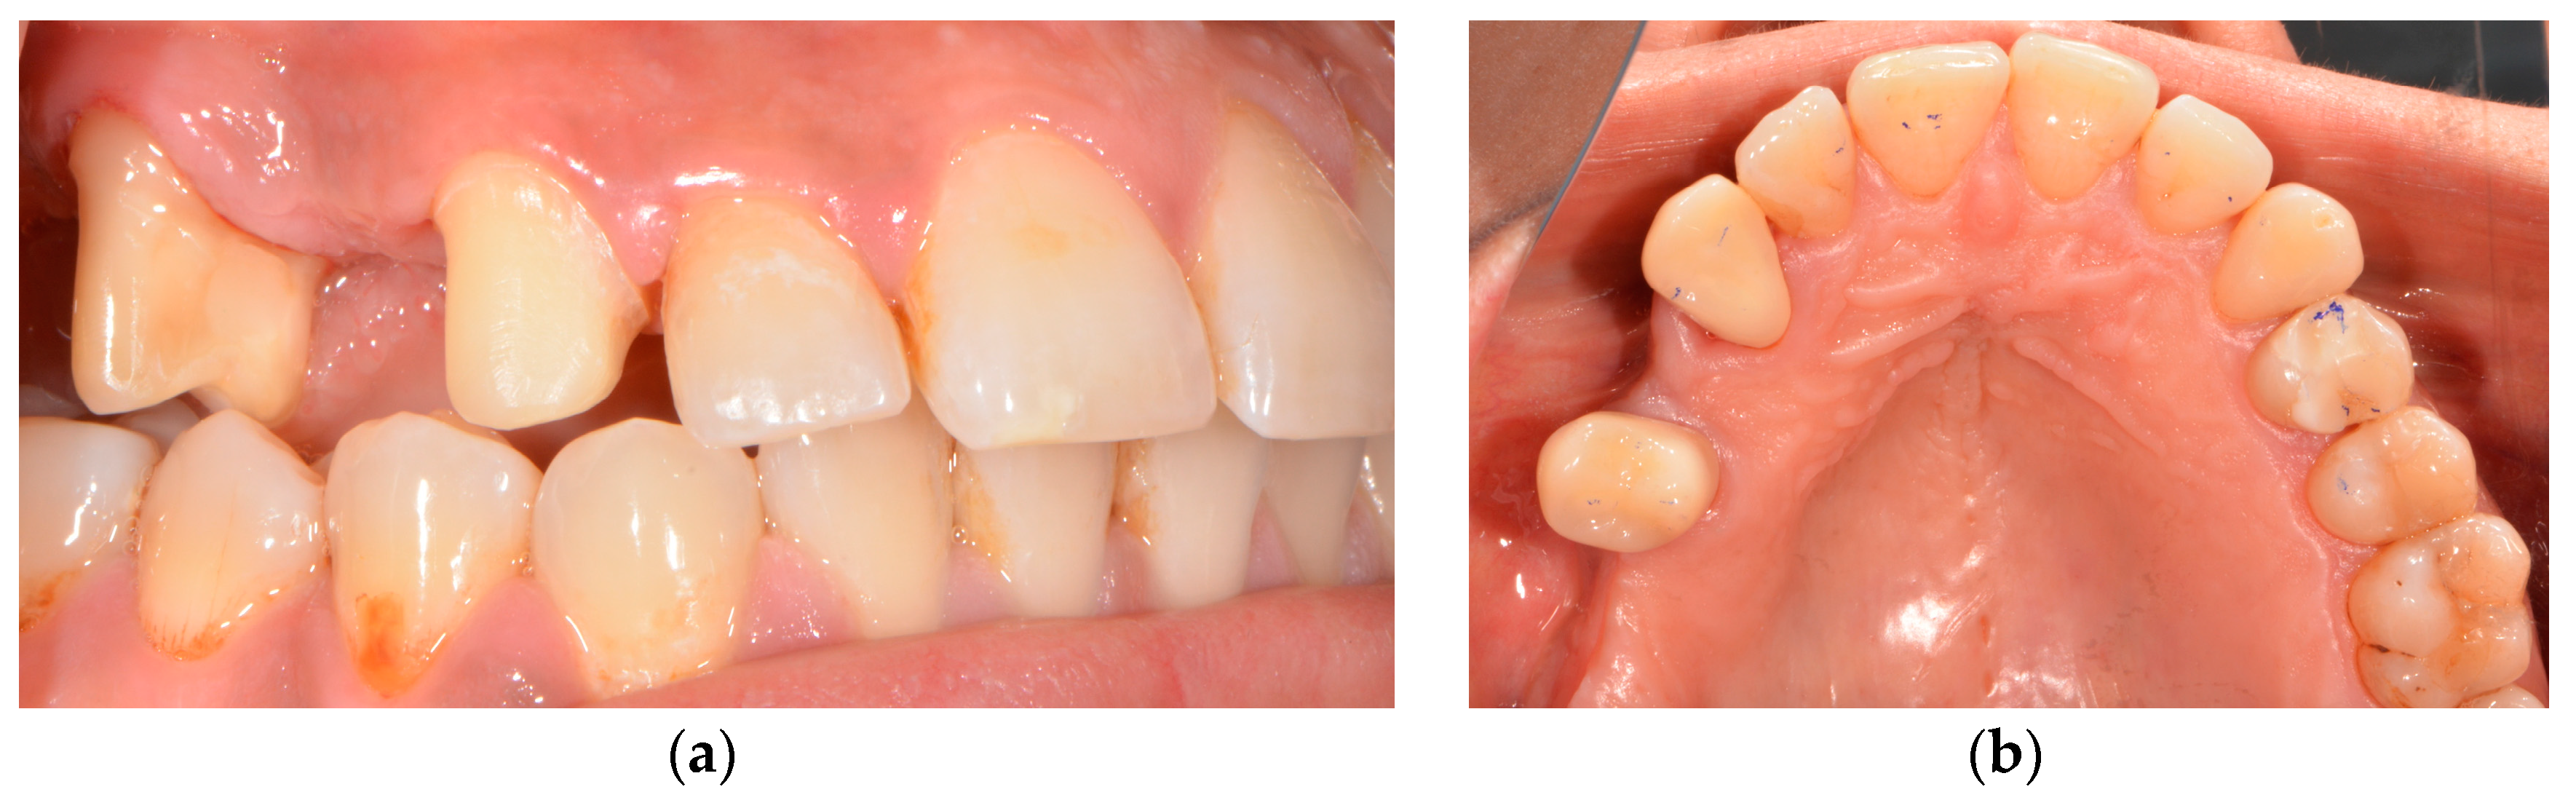

2. Case Report

3. Diagnostic and Planning Procedures

| Gender | female |

| Age | 32 |

| Implant position | Tooth 14 (upper left first premolar) |